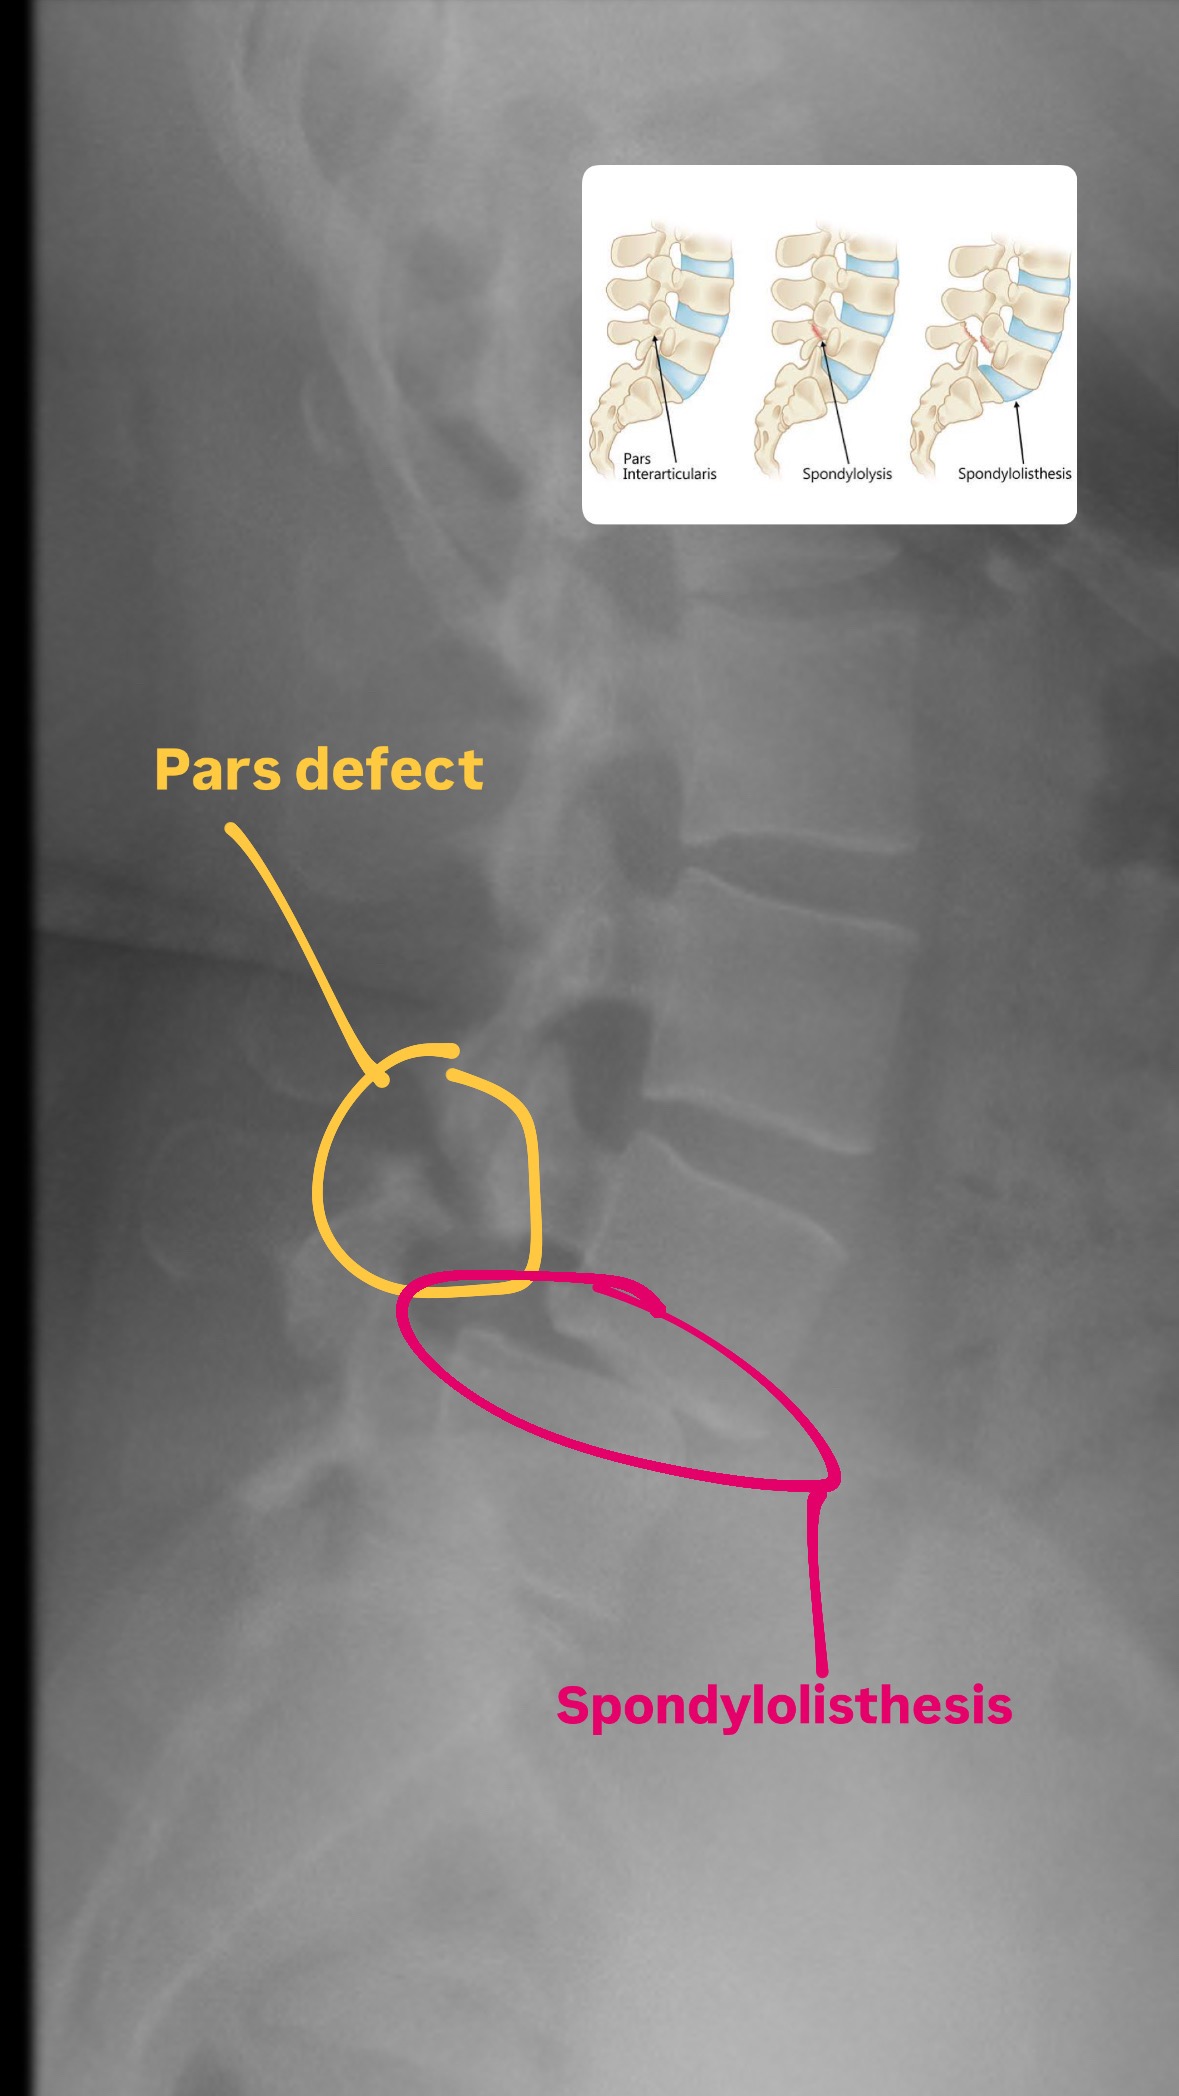

I’ve been diagnosed with a complex and painful spinal condition involving multiple structural issues in my lower back. The main diagnosis is spondylolisthesis and pars defect. A condition where one of my vertebrae has slipped out of place due to a break in the delicate bones of the spine along with anterolisthesis, which means the vertebra is sliding forward (as oppose to retrolisthesis which is backward) and putting pressure on surrounding nerves.

(x-ray taken June 2024)